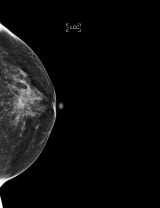

◆유방촬영에서 보이는 하얀 점

유방암 검진을 위해서는 가슴 부위를 압착하듯 눌러 촬영하는 유방 엑스선촬영검사를 받게 된다. 그 결과 석회화가 있다는 의사의 말에 걱정부터 덜컥 앞서는 여성들이 많다. 유방 석회화는 유방 촬영 사진 상 소금가루를 뿌려놓은 듯한 하얀 점들이 보이는 것을 말한다.

석회화는 유방초음파검사로는 잘 보이지가 않고 유방엑스선촬영에서 잘 보이므로, 여성 유방암 검사 시 유방엑스선촬영을 시행하는 것이 좋다.

유방엑스선촬영에서 나타나는 석회화는 그 모양을 보면 암인지 여부를 어느 정도 구별할 수 있다. 그러나 모양만으로는 암인지 여부를 구별할 수가 없는 경우에는 조직검사를 실시해야 한다.